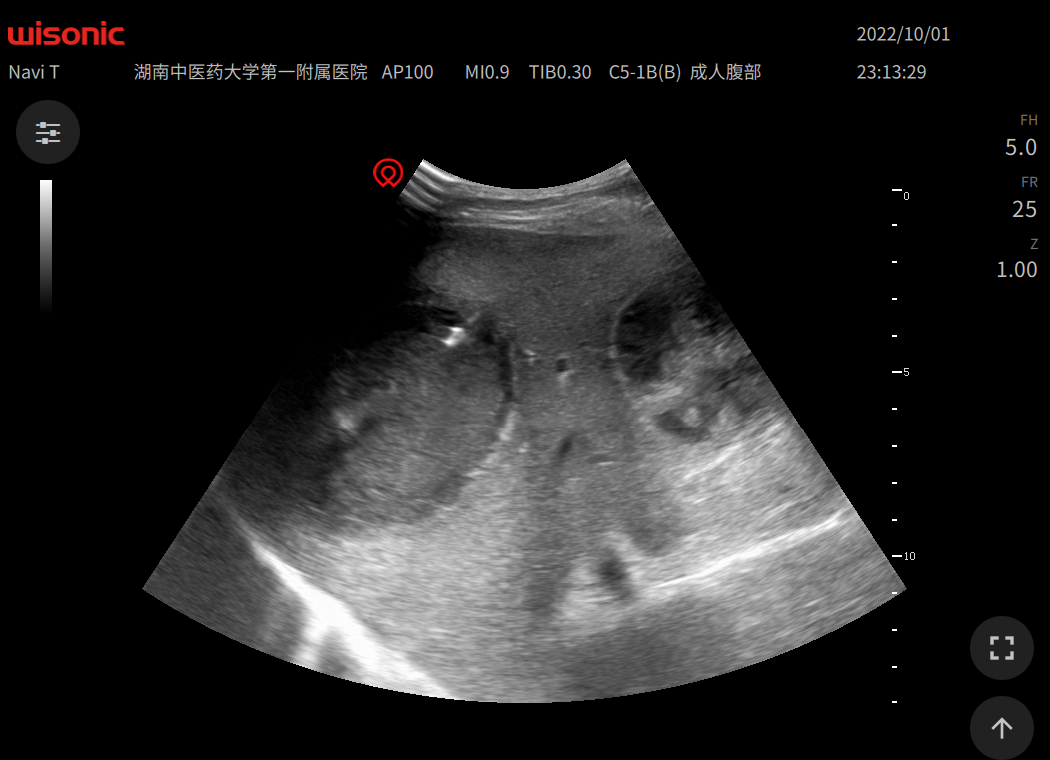

超聲引導(dǎo)下經(jīng)皮肝膽管引流術(shù)(PTCD),梗阻性黃疸退黃效果不錯,圖1-3左肝PTCD,圖2-6左右肝管雙側(cè)PTCD。圖8-9超聲引導(dǎo)下肝腫塊活檢術(shù)。PTCD外引流聯(lián)合ERCP內(nèi)引流已成為我科特色。目前我科開展超聲引導(dǎo)下肝膽胰腫塊活檢術(shù);肝膿腫,腹腔膿腫穿刺引流術(shù);肝囊腫硬化治療術(shù),超聲引導(dǎo)下肝腫瘤微波消融術(shù)。